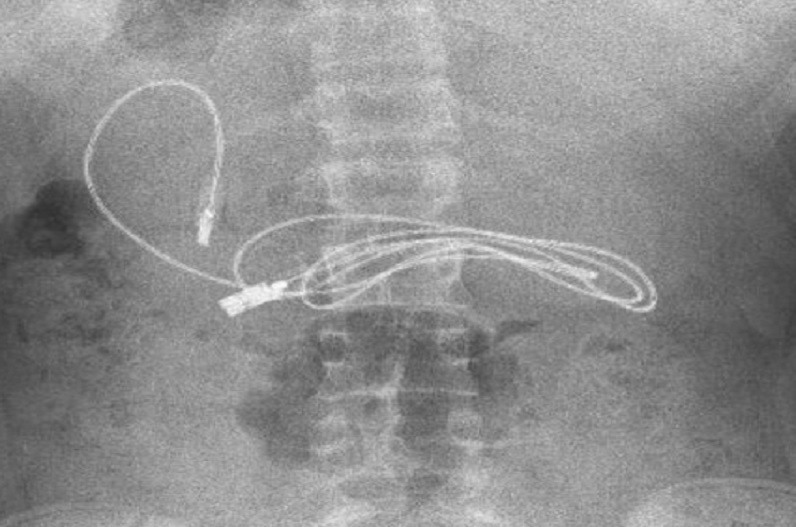

Doctors remove Headphone from child’s जानकारी के अनुसार मामला तुर्की का है। जहां डॉक्टर ने एक बच्चे के पेट से 3 फीट लंबा चार्जिंग केबल और एक हेयरपिन निकाला है। खबर के अनुसार, बच्चे के को पिछले कुछ दिनों से उल्टी और पेट में भयानक दर्द के कारण अस्पताल में भर्ती कराया गया था। जिसके बाद भी बच्चे का पेट दर्द कम नहीं हुआ। जिसके बाद डॉक्टर्स ने बच्चे के पेट का सर्जरी किया। जिसके बाद बच्चे के पेट से 3 फीट लंबा चार्जिंग केबल और एक हेयरपिन देख डॉक्टर भी हैरान हो गया।

आपको बता दें कि तुर्की का रहने वाला बच्चे का उम्र महज 15 साल का है। पिछले कुछ दिनों से बच्चे के पेट में दर्द हो रहा था। जिसके बाद परिजनों ने परेशान होकर बच्चे को इलाज के लिए अस्पताल पहुंचे। जहां डॉक्टर एक्स—रे करवाने की बात कही। जिसके बाद एक्स—रे में बच्चे के पेट से 3 फीट लंबा चार्जिंग केबल और एक हेयरपिन दिखा। फिर डॉक्टरों ने उस बच्चे के पेट की सर्जरी कर सफलतापूर्वक केबल को निकाल दिया। रेपोर्ट्स के मुताबिक़, चार्गिंग केबल के अलावा बच्चे के पेट से एक हैरपिन भी डॉक्टरों ने सर्ज़री के ज़रिए निकला है।